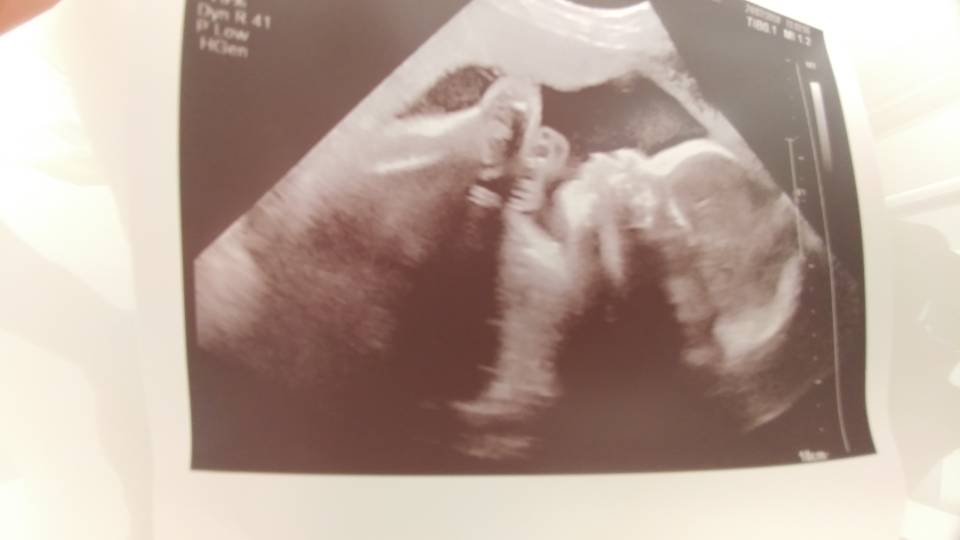

Wow super waga.Hej. Byłam dziś na usg (III prenatalne), u mnie na zwykłym aparacie w ramach abonamentu Medicover, ale lekarz z odpowiednimi certyfikatami.

Dziś 28,1 tc ale synek do przodu z pomiarami o 9 i 10 dni. Waga 1420 g. Wszystko ok, chociaż ułożony poprzecznie twarzą do mojego wnętrza więc bardzo trudno było zmierzyć.

Mówił, że przy takim ułożeniu ruchy mogą być bardzo słabo wyczuwalne i faktycznie nie narzekam na kopniaki.

Także duże ufff

Zobacz załącznik 880906